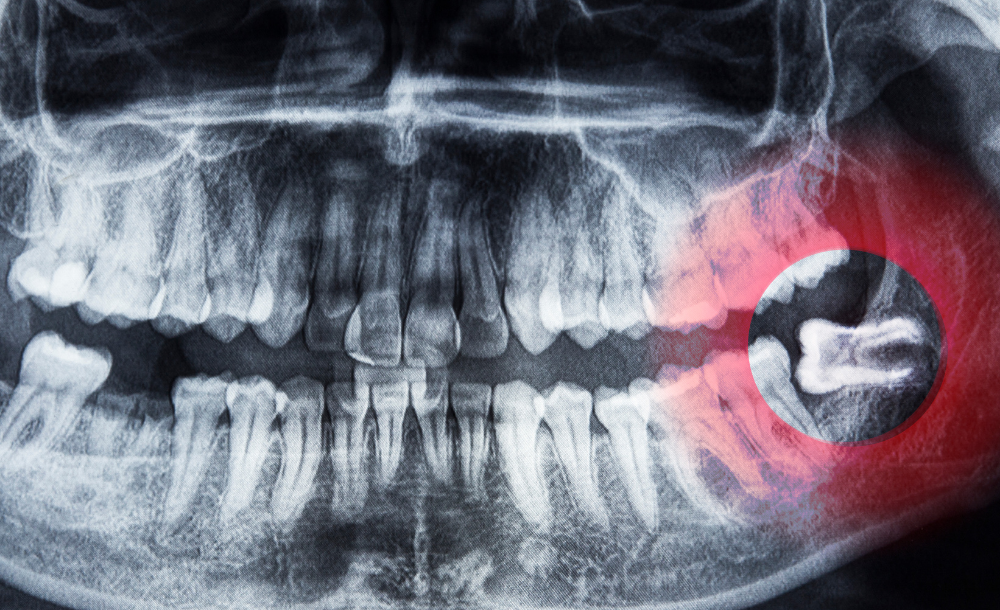

Wisdom teeth, or third molars, usually erupt between the ages of 17 and 25. In many cases, they can cause pain, crowding, infection, or damage to nearby teeth if there isn’t enough space for them to grow properly. At The Family Dental Clinics, we offer safe and comfortable wisdom teeth removal to protect your oral health and relieve discomfort.

Cysts or jaw problems caused by impacted teeth

Consultation & X-rays – To assess position and condition of the teeth